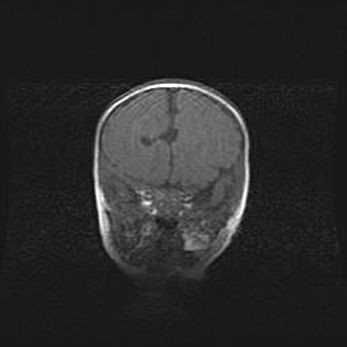

Открытая гидроцефалия.

Возраст: 9 месяцев 12 дней

Вес: 6800 г

Пол: мужской

Окружность головы: 41,5 см

Срок гестации: 28 недель

Гидроцефалия головного мозга у новорожденных имеет характерный признак: опережающий рост окружности головы приводит к визуально хорошо определяемой гидроцефальной форме сильно увеличенного в объёме черепа. Детские неврологи определяют следующие симптомы гидроцефалии у грудничков: выбухающий напряжённый родничок, частое запрокидывание головы, смещение глазных яблок к низу.